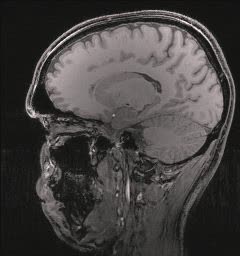

Magnetic Resonance Imaging (MRI)

Magnetic Resonance Imaging is an example of magnetism being applied in the medical field. This technology is a type of medical imaging that uses magnetism and the large percentage of water in the human body to produce detailed images of human body tissue and structures. MRI images are high in contrast, and allow doctors to examine different types of tissues in a region of the body more easily and accurately.

An MRI image of a human head. © Daniel Schwen

MRI machines place the patient in the center a long cylinder surrounded by large, powerful permanent magents, electromagnets, and sometimes superconducting magnets, along with many coils of wire.

Once the body is inside the machine, the water molecules (specifically the hydrogen atoms) inside the body are magnetized in the same direction by a large magnetic field. Then, a radio frequency pulse is directed towards the specific region of the body being examined. Different types of body tissue respond to different frequencies. The radio frequency energizes the hydrogen atoms of a specific tissue and causes them to flip out of alignment from the rest of the hydrogen atoms in the body. When the radio frequency is removed, the disturbed hydrogen atoms slowly return to the magnetized state. As they return to the magnetic field of the machine, they release the energy they recieved from the radio frequency. The coils of wire in the machine detect the energy released, and an image is formed the detected bursts of energy.